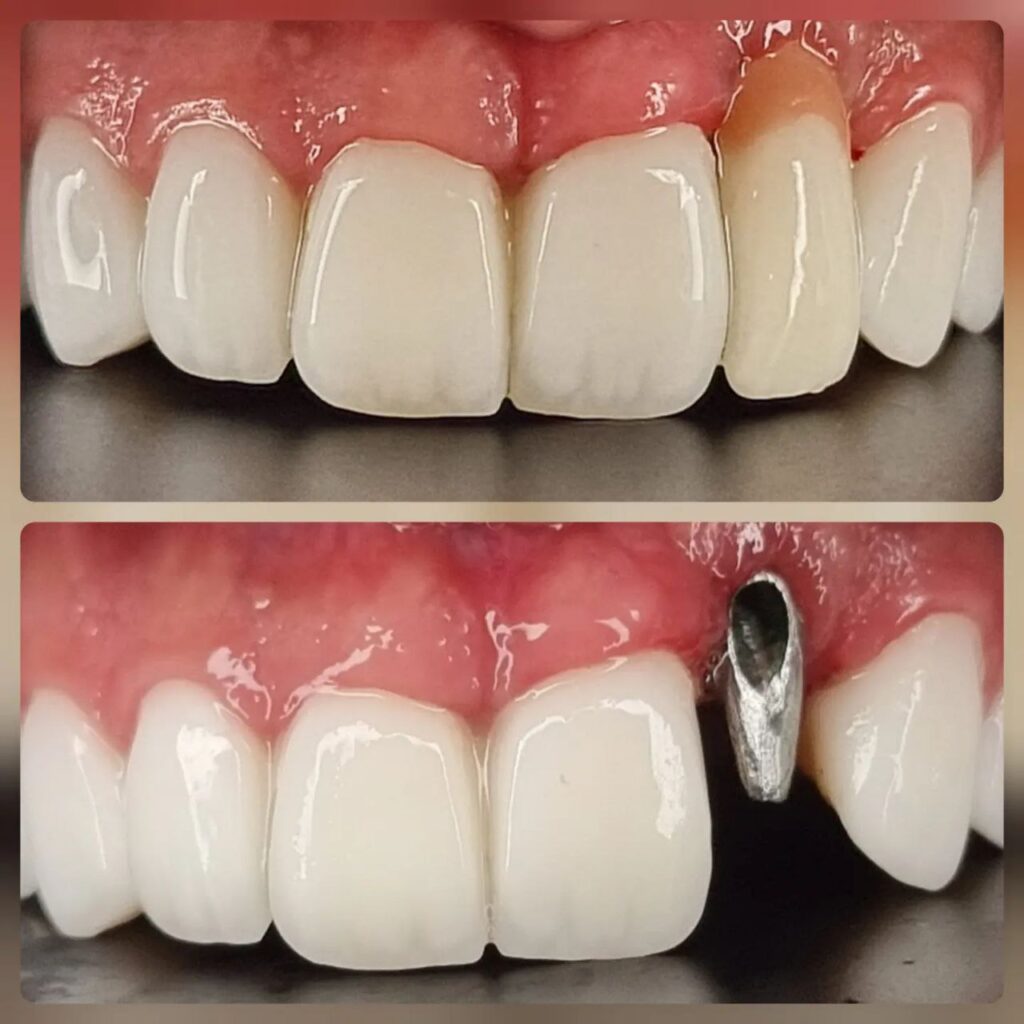

کاشت ایمپلنت دندان

اطمینان حاصل کردن از اینکه دندانهایتان به نحوی زیبا و طبیعی جایگزین شدهاند، از اهمیت بسیاری برخوردار است. ایمپلنت دندان به عنوان یک روش درمانی دائمی در دندانپزشکی شناخته میشود که حاصل آن، یک دندان زیبا و طبیعی در دهان شما خواهد بود.

هرچند که این روش درمانی هزینهی بیشتری نسبت به روشهای دیگر دارد، اما ارزش زیبایی که ایجاد میکند، قابل انکار نیست. ایمپلنتها به قدری شبیه به دندانهای طبیعی هستند که به سختی میتوان آنها را از دیگر دندانها تشخیص داد.